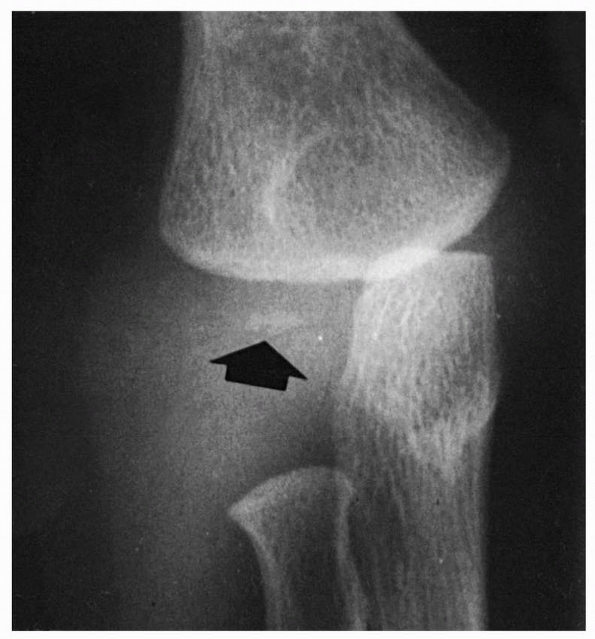

condyle appears just before 1 year of age but may be delayed as late as

18 to 24 months.10 When the nucleus

of the lateral condyle first appears, the distal humeral metaphyseal

border becomes asymmetric. The lateral border slants and becomes

straight to conform with the ossification center of the lateral condyle

(Fig. 13-2). By the end of the second year, this border becomes well defined, possibly even slightly concave. This ossification center

FIGURE 13-2 Ossification at 12 months. As the ossification center of the lateral condyle develops (arrow), the lateral border of the metaphysis becomes straighter.